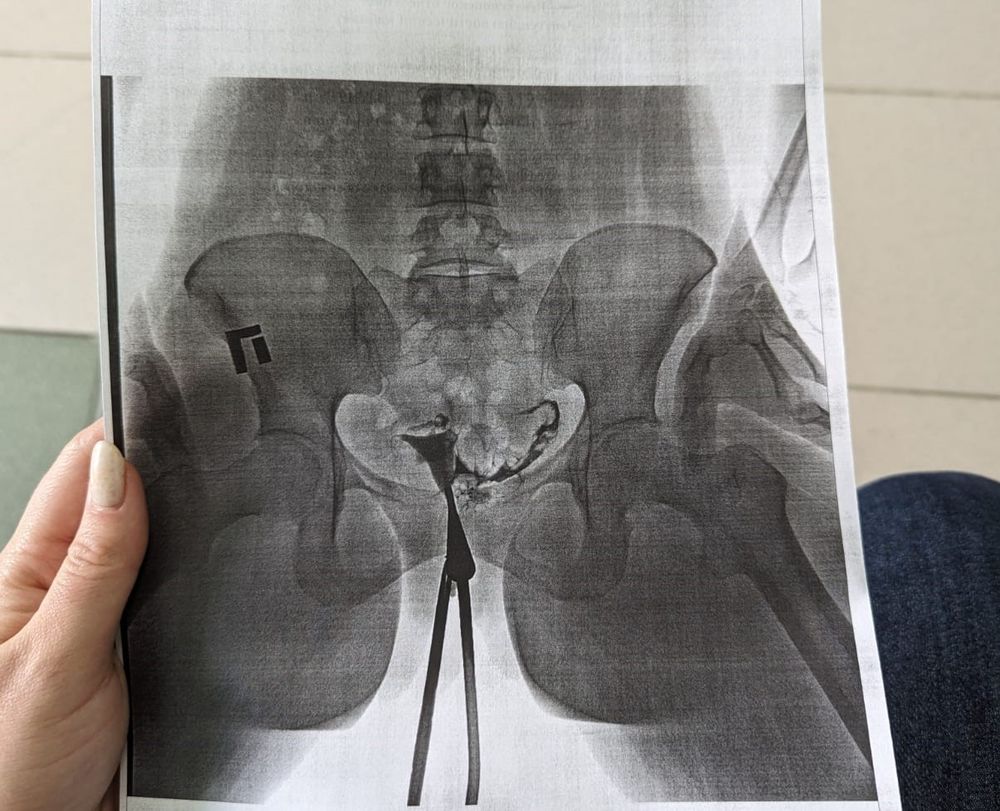

После всего этого я была уверенна, что трубы непроходимы, раз была такая боль. Сходила за снимком, а там:

Трубы проходимы🤞

Смущает, что они длинные, извитые и нитевидные. Но врач сказала, что с такими трубами можно забеременеть.